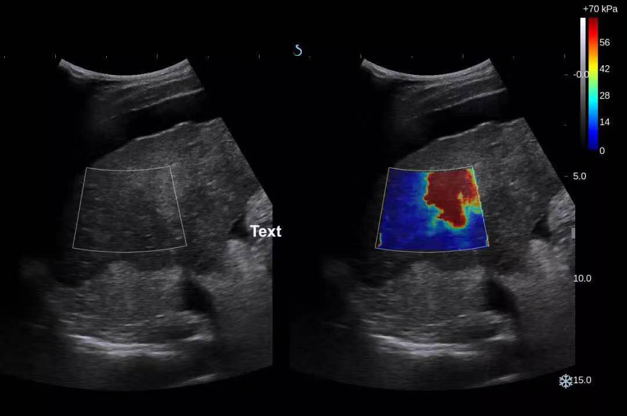

E超,即E成像(SWE,实时剪切波弹性成像技术),是一种测量病变处组织硬度,从而得到弹性数值(杨氏模量)的超声检查新方法。在B超、彩超的基础上利用剪切波去触诊病变部位,并通过不同的颜色和杨氏模量来反映所“触摸”部位的硬度,实现病灶的“声触诊”。

E成像技术用于测量肝脏组织硬度,可应用于各种慢性肝病包括肝纤维化、肝硬化、脂肪肝的定量检测。不需做特殊准备,仅需在常规超声检查基础上叠加剪切波成像技术,就可精准、迅速的获得纤维化病变处的硬度即杨氏模量。杨氏模量值越高,代表该病变处硬度越大,纤维化程度越严重,使肝纤维化与病理相关性更强,并可以依靠此定量依据进行临床治疗及治疗方案的调整。E超的出现弥补了常规检查的不足,具有无创、定量、可重复性高的优点,不仅如此,通过E超测量肝脏、脾脏硬度,可以评估门脉高压并发症的发生风险。

图1

如上图所示,颜色由蓝到黄,杨氏模量测值由小到大,表示了慢性肝病患者从F1期(轻度肝纤维化)到F4期(肝硬化)肝脏硬度的改变